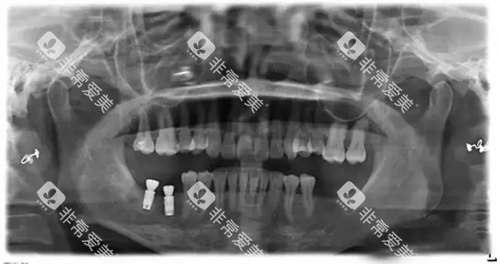

超全的口腔检查

在决定种美格真种植牙之前,一定要做一个超全的口腔检查。医生会检查患者的牙齿、牙槽骨、牙龈等情况,看看是否适合种牙。通过口腔检查,医生还能了解患者的具体问题,制定出比较适合患者的种牙方案。比如说拍牙片、做CT等检查,这些都能帮助医生更较准地了解患者的口腔状况。